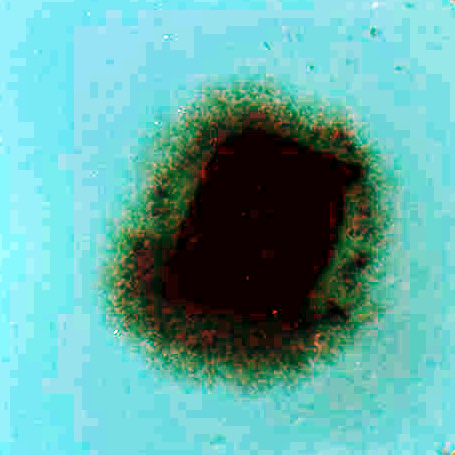

The migration activity of splenocytes [5] derived from rabbit spleen fragments was determined as follows. Aseptically excised rabbit (Chinchilla) spleen was cut on a sterile paraffin plate into pieces 1 mm in diameter. These fragments were washed in minimal essential medium (MEM). Increasing concentrations of the additives (photosensitizers, phthalhydrazide, CuSO4, H2O2) in MEM with 10% fetal calf serum (FCS) were pipetted in volumes of 0,2 mL into wells (plates 8x12, flat bottom). Each combination of the additives was placed into four wells; one fragment was transferred into each well. The fragments in cultivation medium only were used as a control. After 24 hours of cultivation at 37oC in 5% CO2, the migration zones of the spleen cells were measured [5]. The results are presented as the migration index (MI) - the ratio between the experimental migration zone (Fig.I.B.) to the control zone (Fig.I.A.). Compounds were tested in two independent experiments in triplicate.

Figure I. Fragments of the rabbit's spleen splenocytes

A. …………………………………………………………………..B.

………………………………………..

As a first

we confirmed that the photosensitizers chemiexcited by phthalhydrazide can produce the photodynamic damage on the rabbit’s spleen (test of vitality of the migration activity of splenocytes derived from rabbit's spleen fragments).This test turned up to be the simple, versatile and reliable for photodynamic effect in connection with sensitized chemiluminescence. For the dependence on the elementary concentrations of the photosensitizer, compounds of the chemiluminescent system and on their combinations, the data display the changes of the migration index. The changes can be neglected for the compounds of the chemiluminescent system but they are significant for the individual photosensitizer and its combination with the chemiluminescent compounds. Dependencies of MI on the photosensitizer concentration, eventually on the photosensitizer concentration at the presence of compounds of the chemiluminescent system, complied with simple Langmuir isotherms. For this reason we were able to assume that photosensitizer is adsorbed in the biological membrane and the presented data indicate that observed lethality is a result of photodynamic effect.